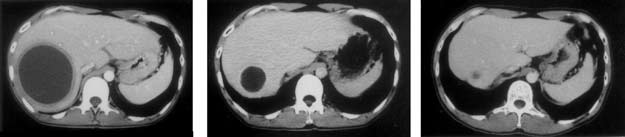

図5.赤痢アメーバ性肝膿瘍の治療によるCT像の変化

この症例はメトロニダゾールのみで治療され、穿刺やドレナージによる排液は行われなかった。治療終了後に長時間を経て膿瘍が吸収され縮小してゆくことが分かる。左から治療前、治療3カ月後、治療1年後。

超音波やCT検査による膿瘍の証明をする。本法では膿瘍である可能性を示唆することはできても、病原体診断は得られないが、肝右葉に形成された円形~楕円形膿瘍はアメ-バ性である可能性が高い(図5)。